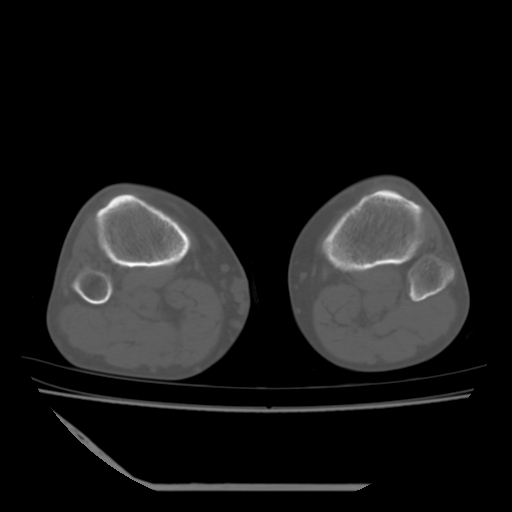

标题: CT13225:老年男性,左膝关节疼痛数月;请各位老师讨论。 [打印本页]

标题: CT13225:老年男性,左膝关节疼痛数月;请各位老师讨论。

骨质增生,骨性关节面硬化,关节积液,考虑退行性骨关节病

关节腔内少量积液,关节面退变。

双膝退变

骨质增生,骨性关节面硬化,关节间隙失常,关节积液,考虑退行性骨关节病.

这是由于两侧的肌肉不对称所致,加上扫描的平面也有些差异。请看示意图:

这个病例诊断:退行性骨关节炎